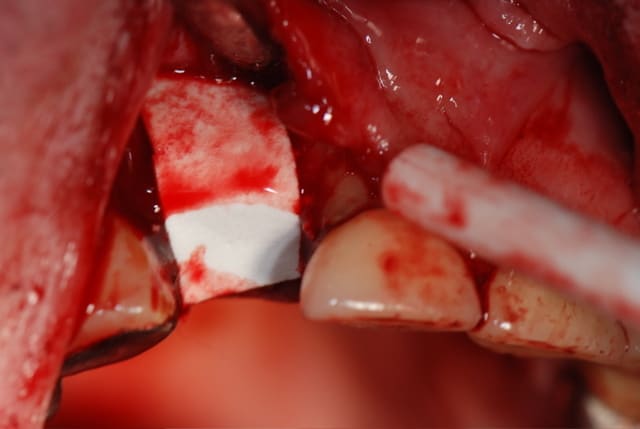

finalement, ça s'est terminé par une E. mais pas de I.I. ni de temporisation immédiate du tout malheureusement; par contre, pose de membrane et de ß TCP; voici les photos; ah oui, photo aussi d'une endo top de top (c'est pas moi, c'est pas moi!); l'extraction s'est faite avec un kit de piezo que l'on m'a prêté pour essai, c'est génial de chez génial, très très peu de délabrement, ostéotomie très fine, danger inexistant, je suis séduit

on voit sur la photo de l'alvéole vide en palatin le début de"trou" que j'ai fait, il faut se méfier du piezo quand même, c'est à la fois très sécurisant mais c'est aussi puissant, la preuve, il faut donc continuer à réfléchir, pfffff, et la suite arrive

après forage du puit en ø 3, j'ai testé le site et j'ai compris tout de suite que ça n'allait sans doute pas se passer comme d'habitude, le foret bougeait trop à 15 mm; j'ai quand même continué en ø 4 et mis le taraud pour voir; ça a bien bloqué mais j'étais sceptique; le problème, c'est que ça saignait aussi de façon anormale; j'ai donc décidé de soulever le lambeau en PE pour voir ce qui se passait....je n'ai pas été déçu; j'ai cureté le TG qui était externe à l'alvéole, j'aurais d'ailleurs pû y penser tout de suite en voyant la racine, et j'ai changé d'objectif : plus d'implant mais comblement seul; j'ai refermé avec le TCP et la membrane de collagène que j'ai quasiment intégralement recouverte par un lambeau d'épaisseur partielle; la membrane devrait s'exposer un peu mais ça se gère habituellement sans problème